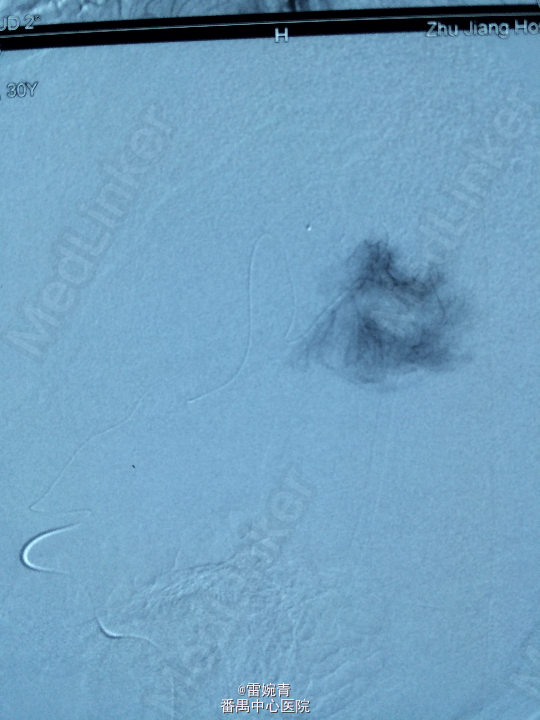

诊断:脑膜瘤 处理:先行DSA检查以明确脑膜瘤的供血动脉情况,见:肿瘤染色,肿瘤主要由左侧眼动脉供血,用Glubran胶将其闭塞,后择期行手术切除治疗。术后病理证实为脑膜瘤。

术后患者病情稳定,后出院。 讨论:脑膜瘤可由颈内颈外动脉双重动脉供血,血供较为丰富,直接开颅手术治疗出血量较多,如果能术前行介入栓塞治疗可减少书中出血量,并降低手术风险及难度。